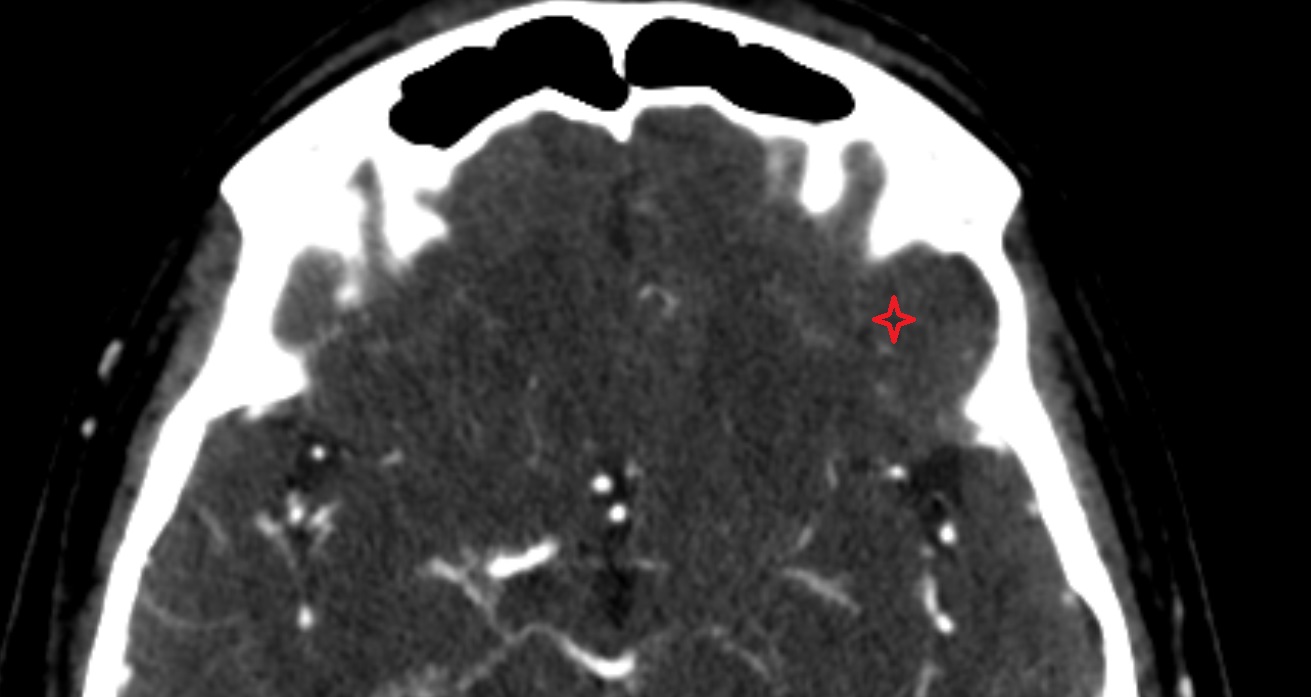

- Lateral sulcus (Sylvian fissure)